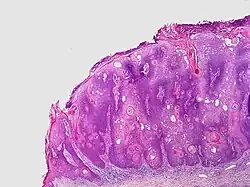

Seborrheic keratosis close-up

Visual diagnosis is made by the "stuck on" appearance, horny pearls or cysts embedded in the structure. Darkly pigmented lesions can be challenging to distinguish from nodular melanomas.[10] Furthermore, thin seborrheic keratoses on facial skin can be very difficult to differentiate from lentigo maligna even with dermatoscopy. Clinically, epidermal nevi are similar to seborrheic keratoses in appearance. Epidermal nevi are usually present at or near birth. Condylomas and warts can clinically resemble seborrheic keratoses, and dermatoscopy can be helpful to differentiate them. On the penis and genital skin, condylomas and seborrheic keratoses can be difficult to differentiate, even on biopsy.

A study examining over 4,000 biopsied skin lesions identified clinically as seborrheic keratoses showed 3.1% were malignancies. Two-thirds of those were squamous cell carcinoma.[11] To date, the gold standard in the diagnosis of seborrheic keratosis is represented by the histolopathologic analysis of a skin biopsy.[12]